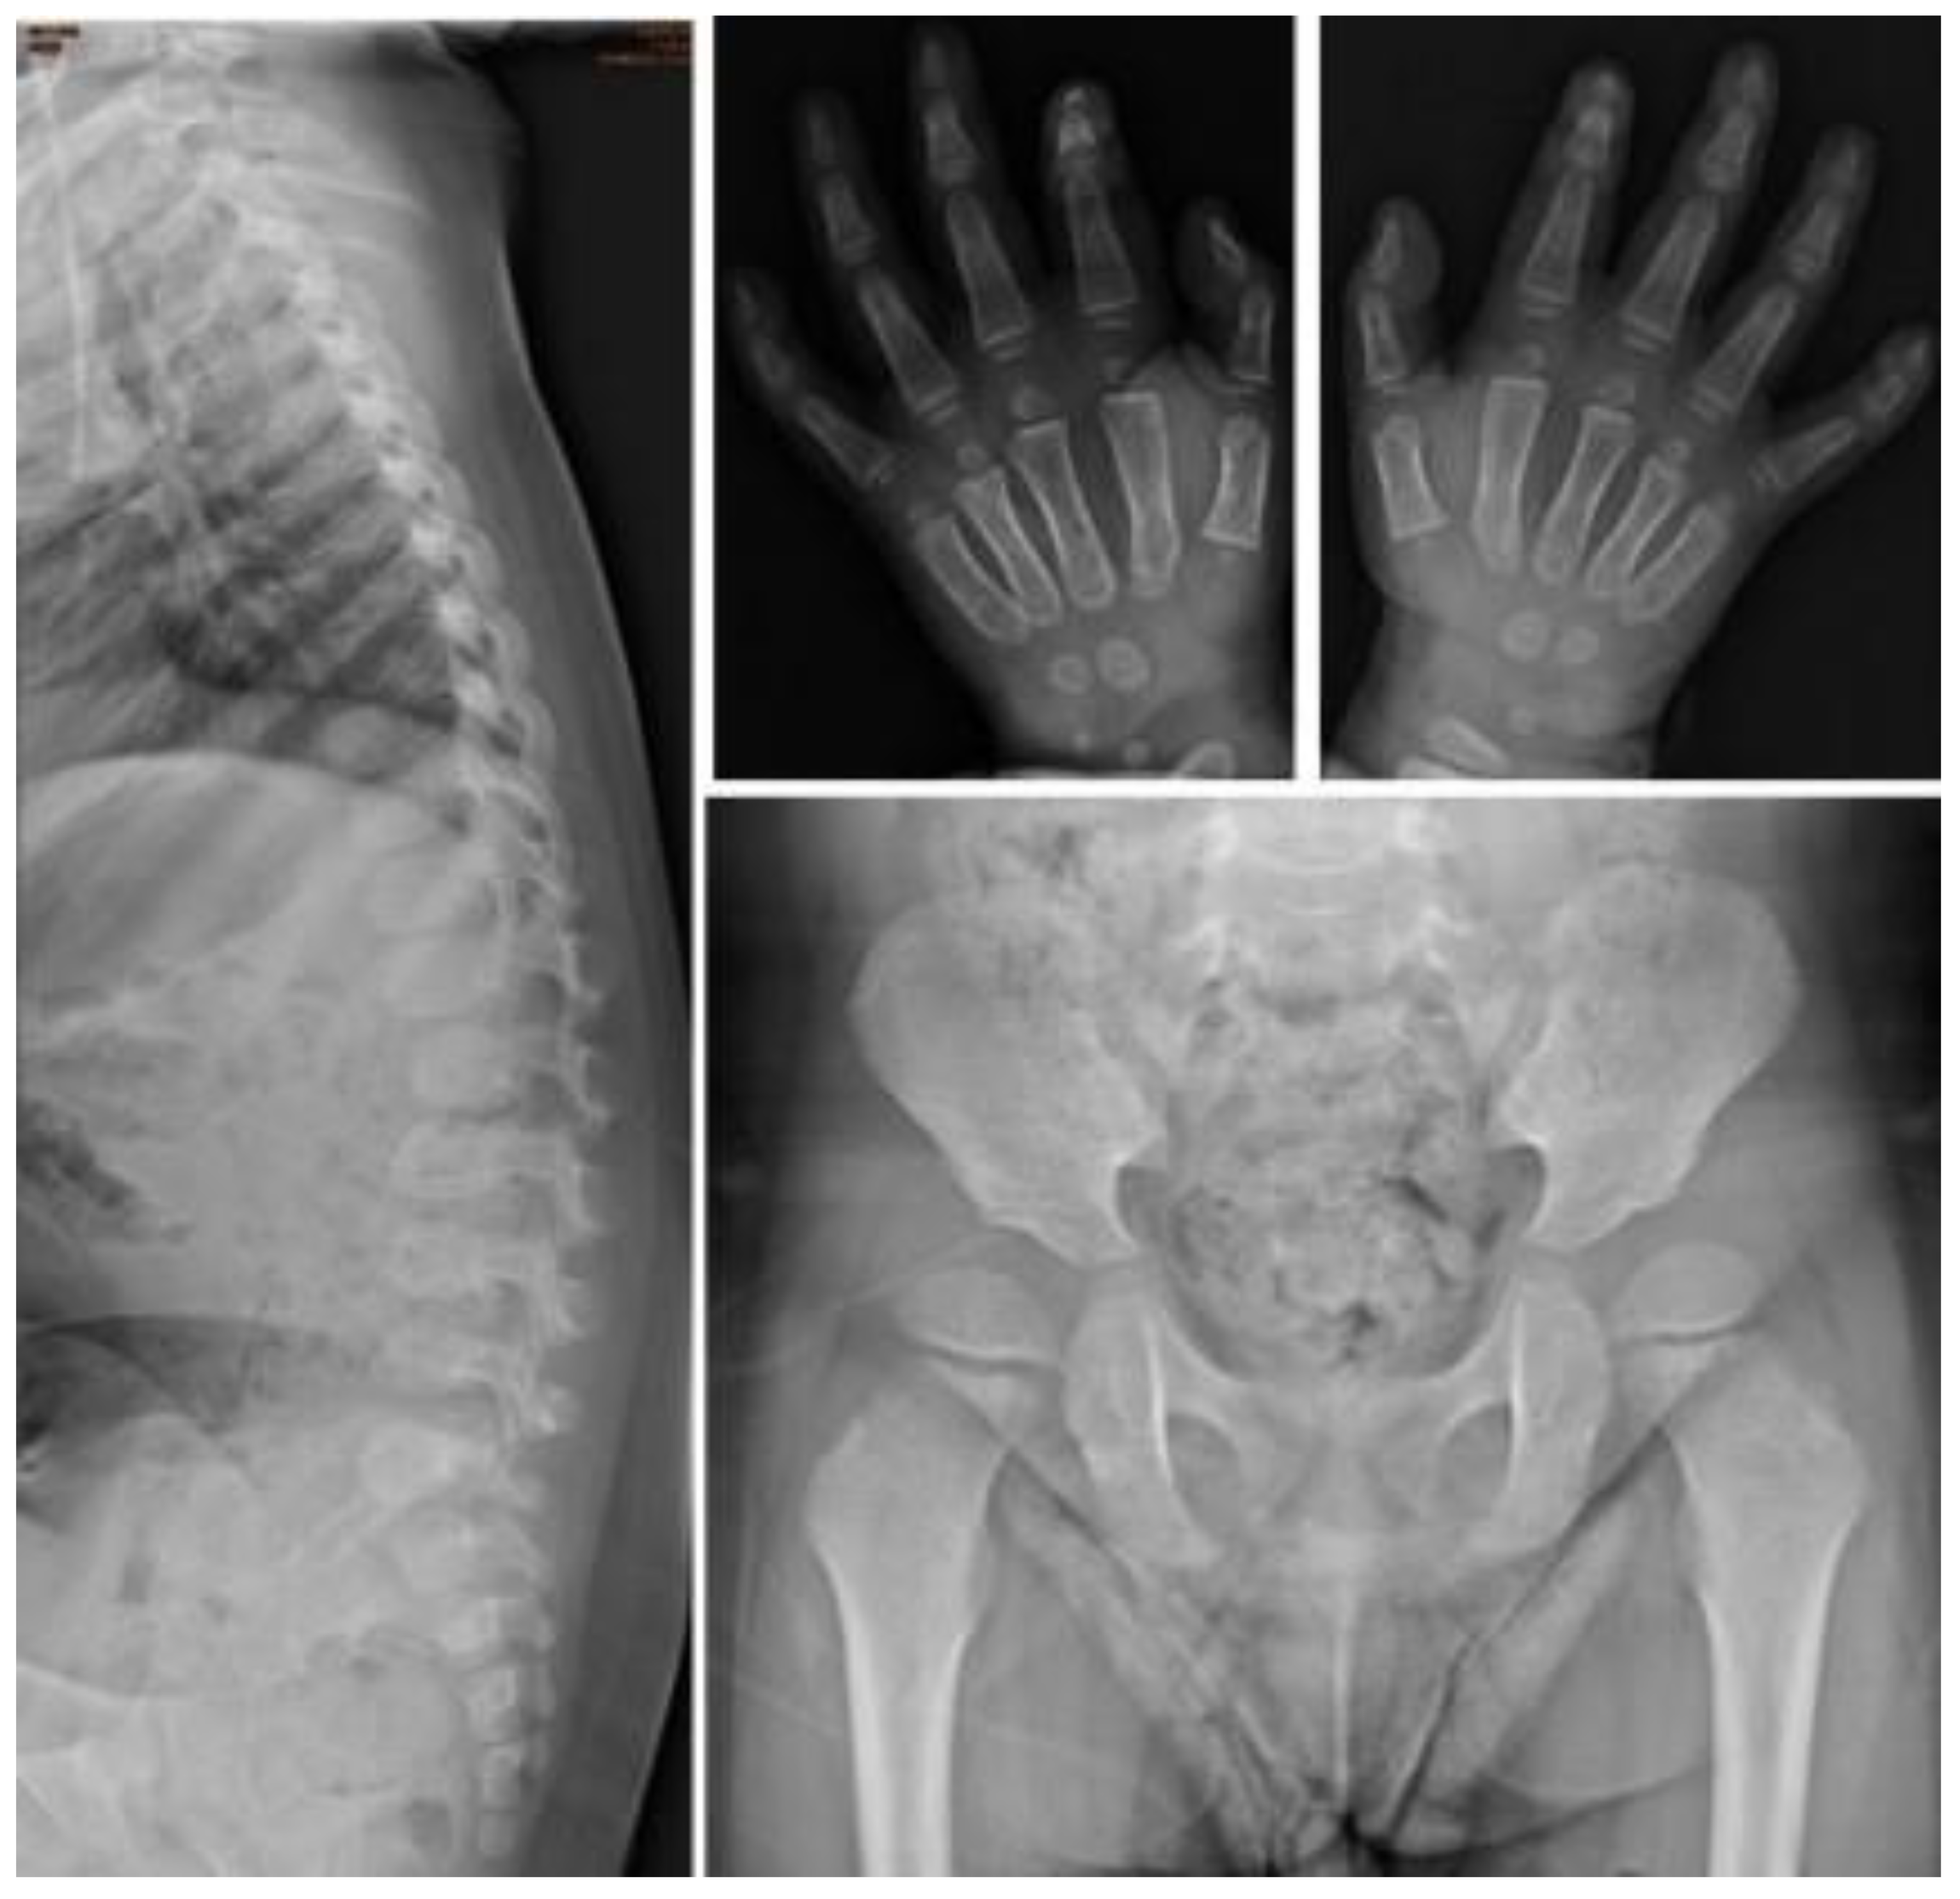

| I-6 | M | c.1007–1666_c.1180 + 2113 delinsTT | 0.9 | 0.4 | Baseline | 0.1 | 0.99 | 177.96 | 30.77 | 203.35 | 0.31 | Normal | Normal | Normal | ASD II | Normal |

| Follow-up | 2.8 | 110.92 | 8.9 | 0.1 | 20.64 | 7.05 | Persistent proximal pointed metacarpal and bullet-shaped phalanges of both hands. | Anterior beaking of lower thoracic to lumbar vertebrae. Relative enlargement of sternal end of bilateral clavicles. | Shallow bilateral acetabuli and coxa valga of both femurs. | ASD II, MR, AR | Mild splenomegaly | |||||